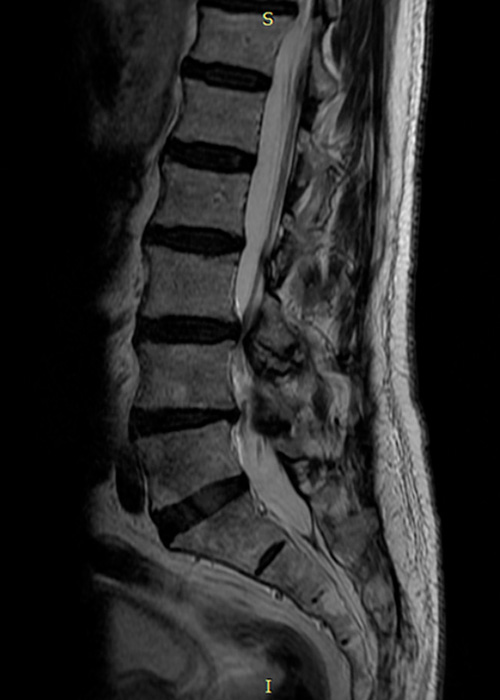

Tras las pruebas pertinentes y el exhaustivo estudio de su caso se le indica la necesidad de una cirugía de columna con nuestro método personal de Endoscopia Avanzada de Columna mínimamente invasiva para que recupere su vida y pueda olvidarse del dolor.

estenosis de canal radiografia

Cirugia de columna para estenosis de canal